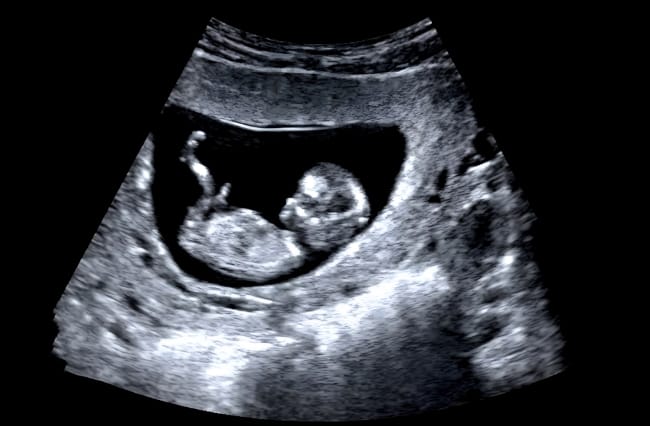

Janin 36 minggu menandakan bahwa kandungan Bumil sudah menginjak usia 8 bulan. Pada usia kehamilan ini, berat normal janin 36 minggu umumnya berkisar antara 2,5–2,7 kg, dengan panjang dari kepala hingga tumit sekitar 47 cm. Ukuran ini kurang lebih setara dengan buah blewah besar.

Namun, jika berat janin usia 36 minggu kurang dari 2,2 kg atau melebihi 3 kg, dokter biasanya akan merekomendasikan pemeriksaan lanjutan, seperti USG serial dan pemantauan aliran darah plasenta, untuk memastikan kondisi janin tetap sehat.